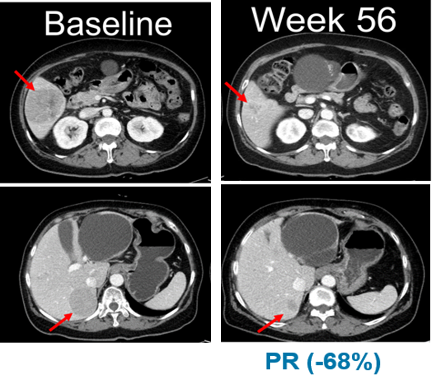

±× °á°ú, ÀûÀÀÁõ È®Àå ÀÓ»óÀÇ NRAS º¯ÀÌ Èæ»öÁ¾ ¿¬±¸¿¡¼´Â 13¸íÀÇ È¯ÀÚ Áß 5¸íÀÌ ºÎºÐ¹ÝÀÀ(PR)À» º¸¿´À¸¸ç, ÃÖ°í¹ÝÀÀ·ü(BORR)Àº 38.5%·Î ³ªÅ¸³µ´Ù.

13¸íÀÇ È¯ÀÚ Áß 11¸íÀº ÀÌÀü¿¡ ¸é¿ª°ü¹®¾ïÁ¦Á¦(CPI)¸¦ Åõ¿© ¹Þ¾ÒÀ¸¸ç, ¸é¿ª°ü¹®¾ïÁ¦Á¦ Åõ¿© ȯÀÚ±º ´ë»ó ÃÖ°í¹ÝÀÀ·ü(BORR)Àº 45.5%·Î È®ÀεƴÙ. ¹«ÁøÇà»ýÁ¸±â°£(PFS)ÀÇ Áß°£°ªÀº 7.3°³¿ùÀÌ´Ù.